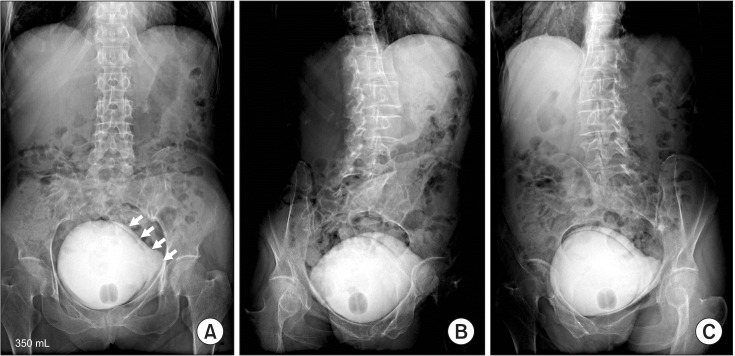

عکس رنگی مثانه در عکس رنگی مثانه ماده حاجب به صورت ترکیبی با نرمال سالین از طریق سوند وارد مثانه بیمار میشود، و گرافی های متعدد در شرایط پربودن مثانه، و حین ادرار کردن از بیمار گرفته میشود و مسیر خروجی ادرار بررسی میشود.